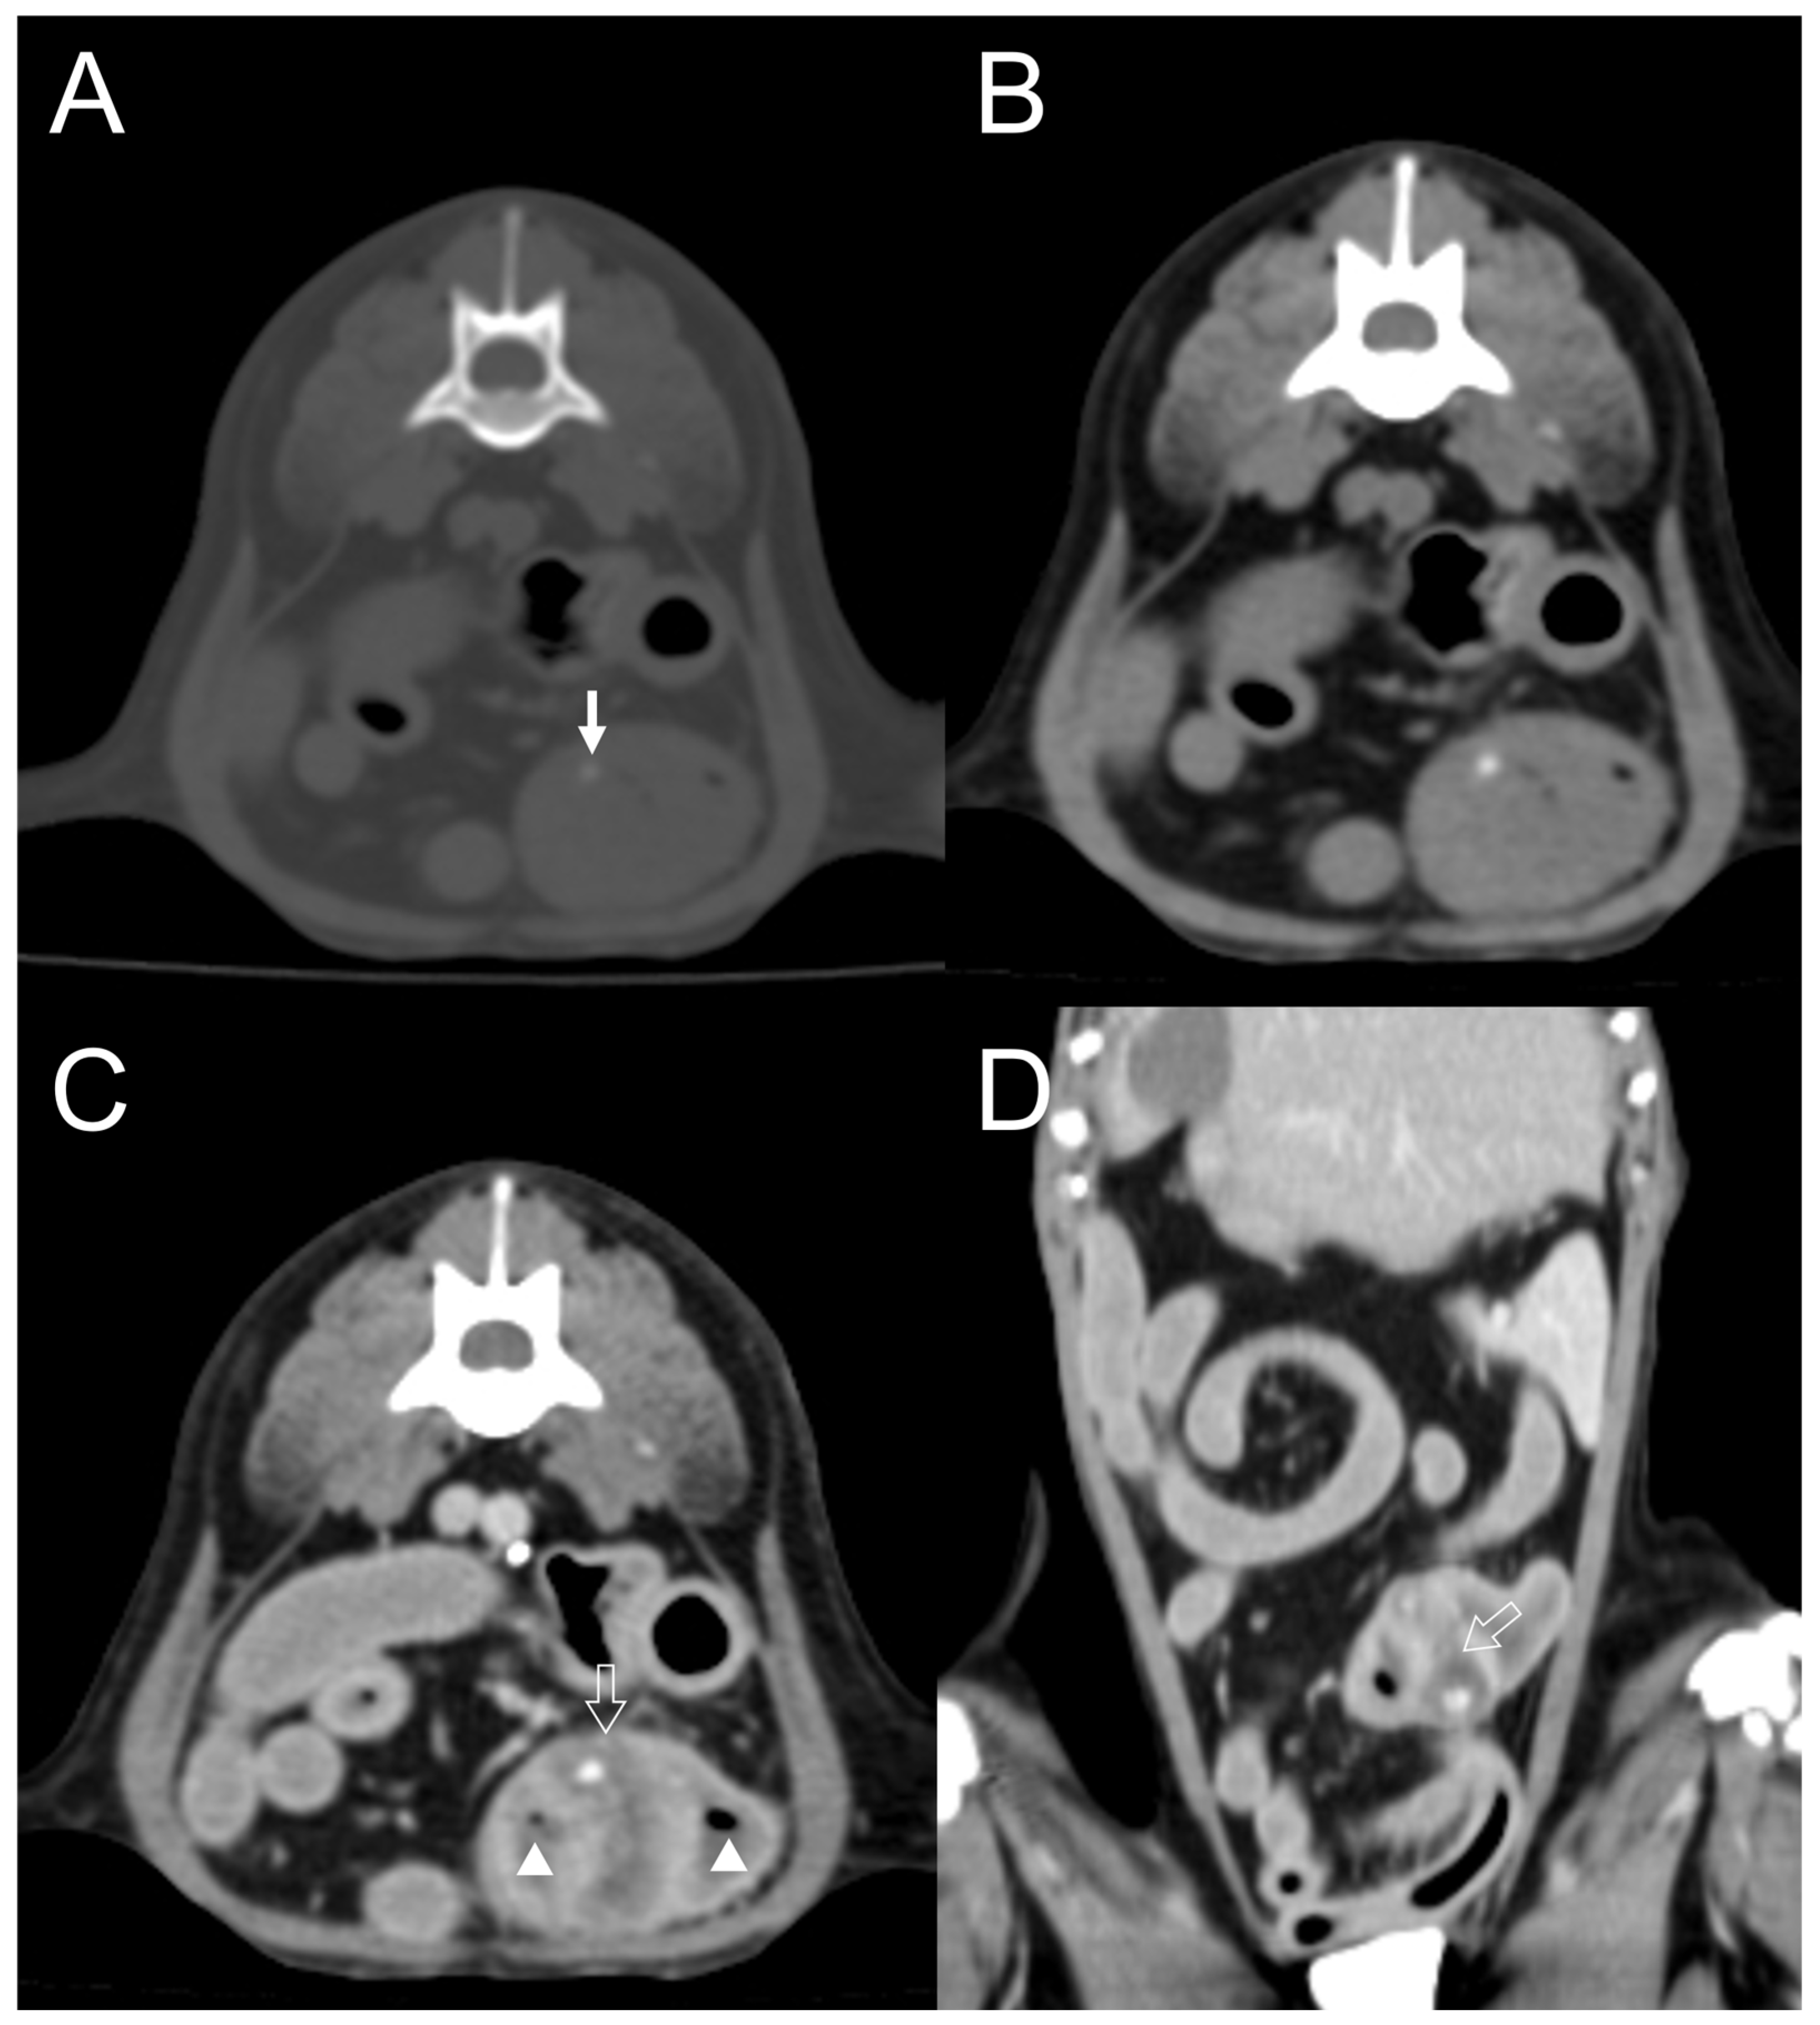

| Dog 6 | Small intestine | Well-defined | Homogenous | Absent | Present | Mild | Dot | Eccentric |